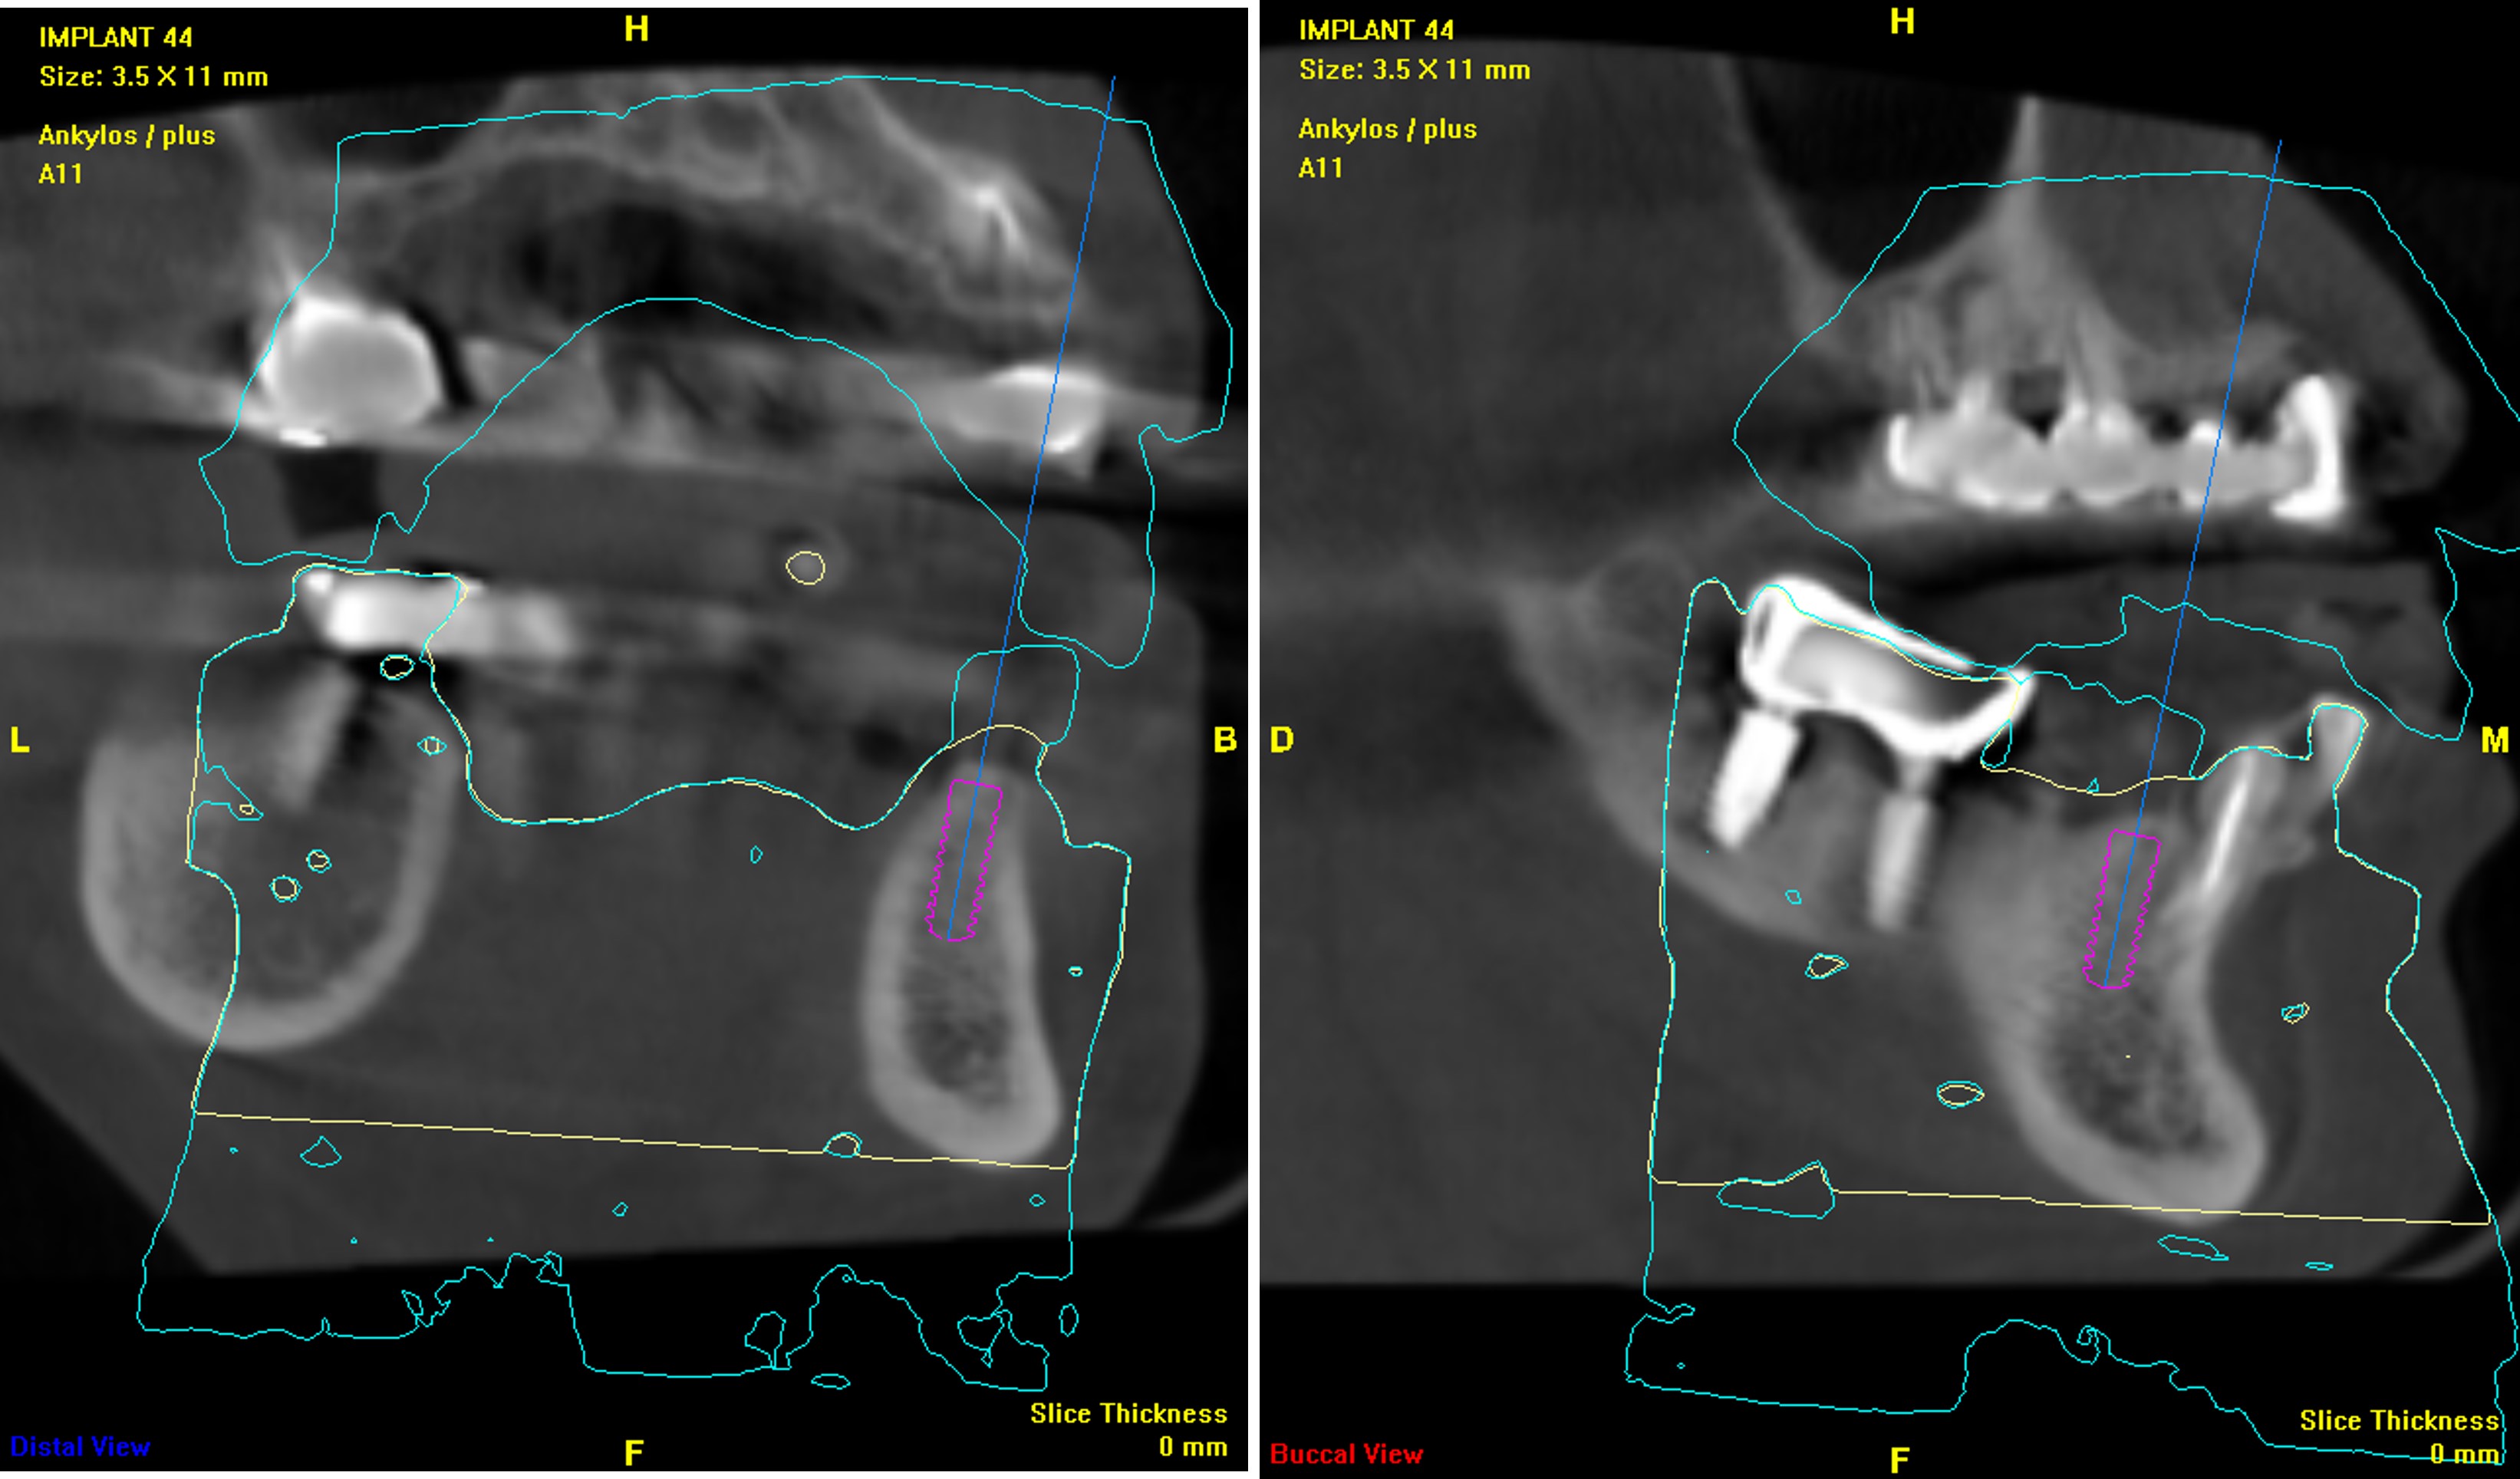

電腦斷層評估植牙位:#44

電腦斷層評估植牙位:#45